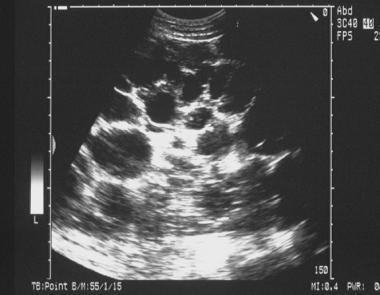

What ‘big’ kidney on USS may indicate?

Polycystic kidney disease - kidney is filled with cysts/ above the centile that is expected for a child at given age